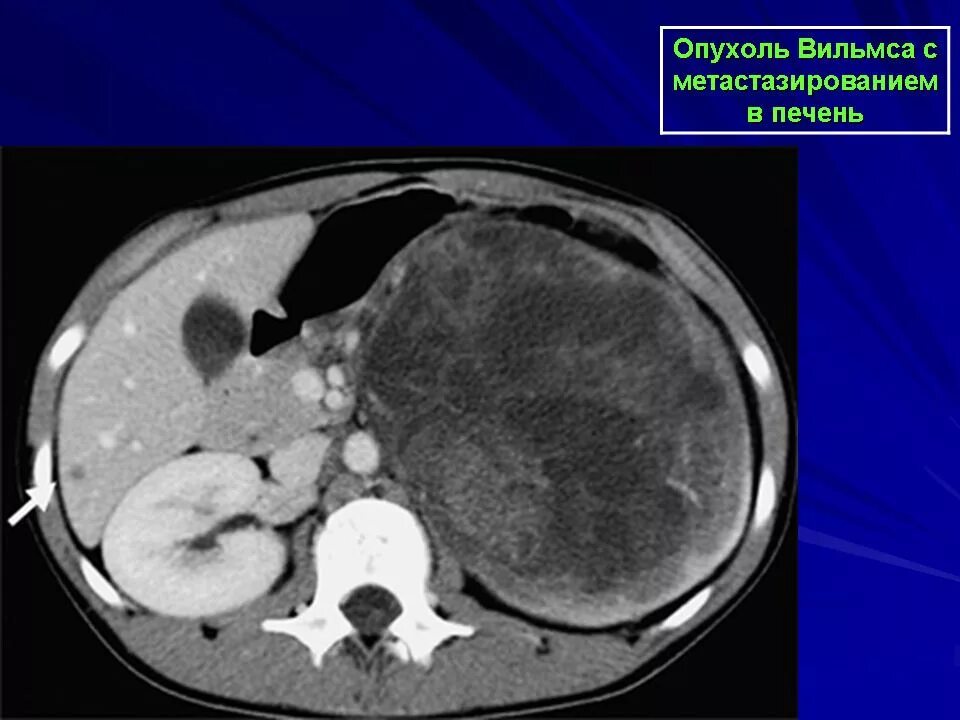

Метастазы рака почки